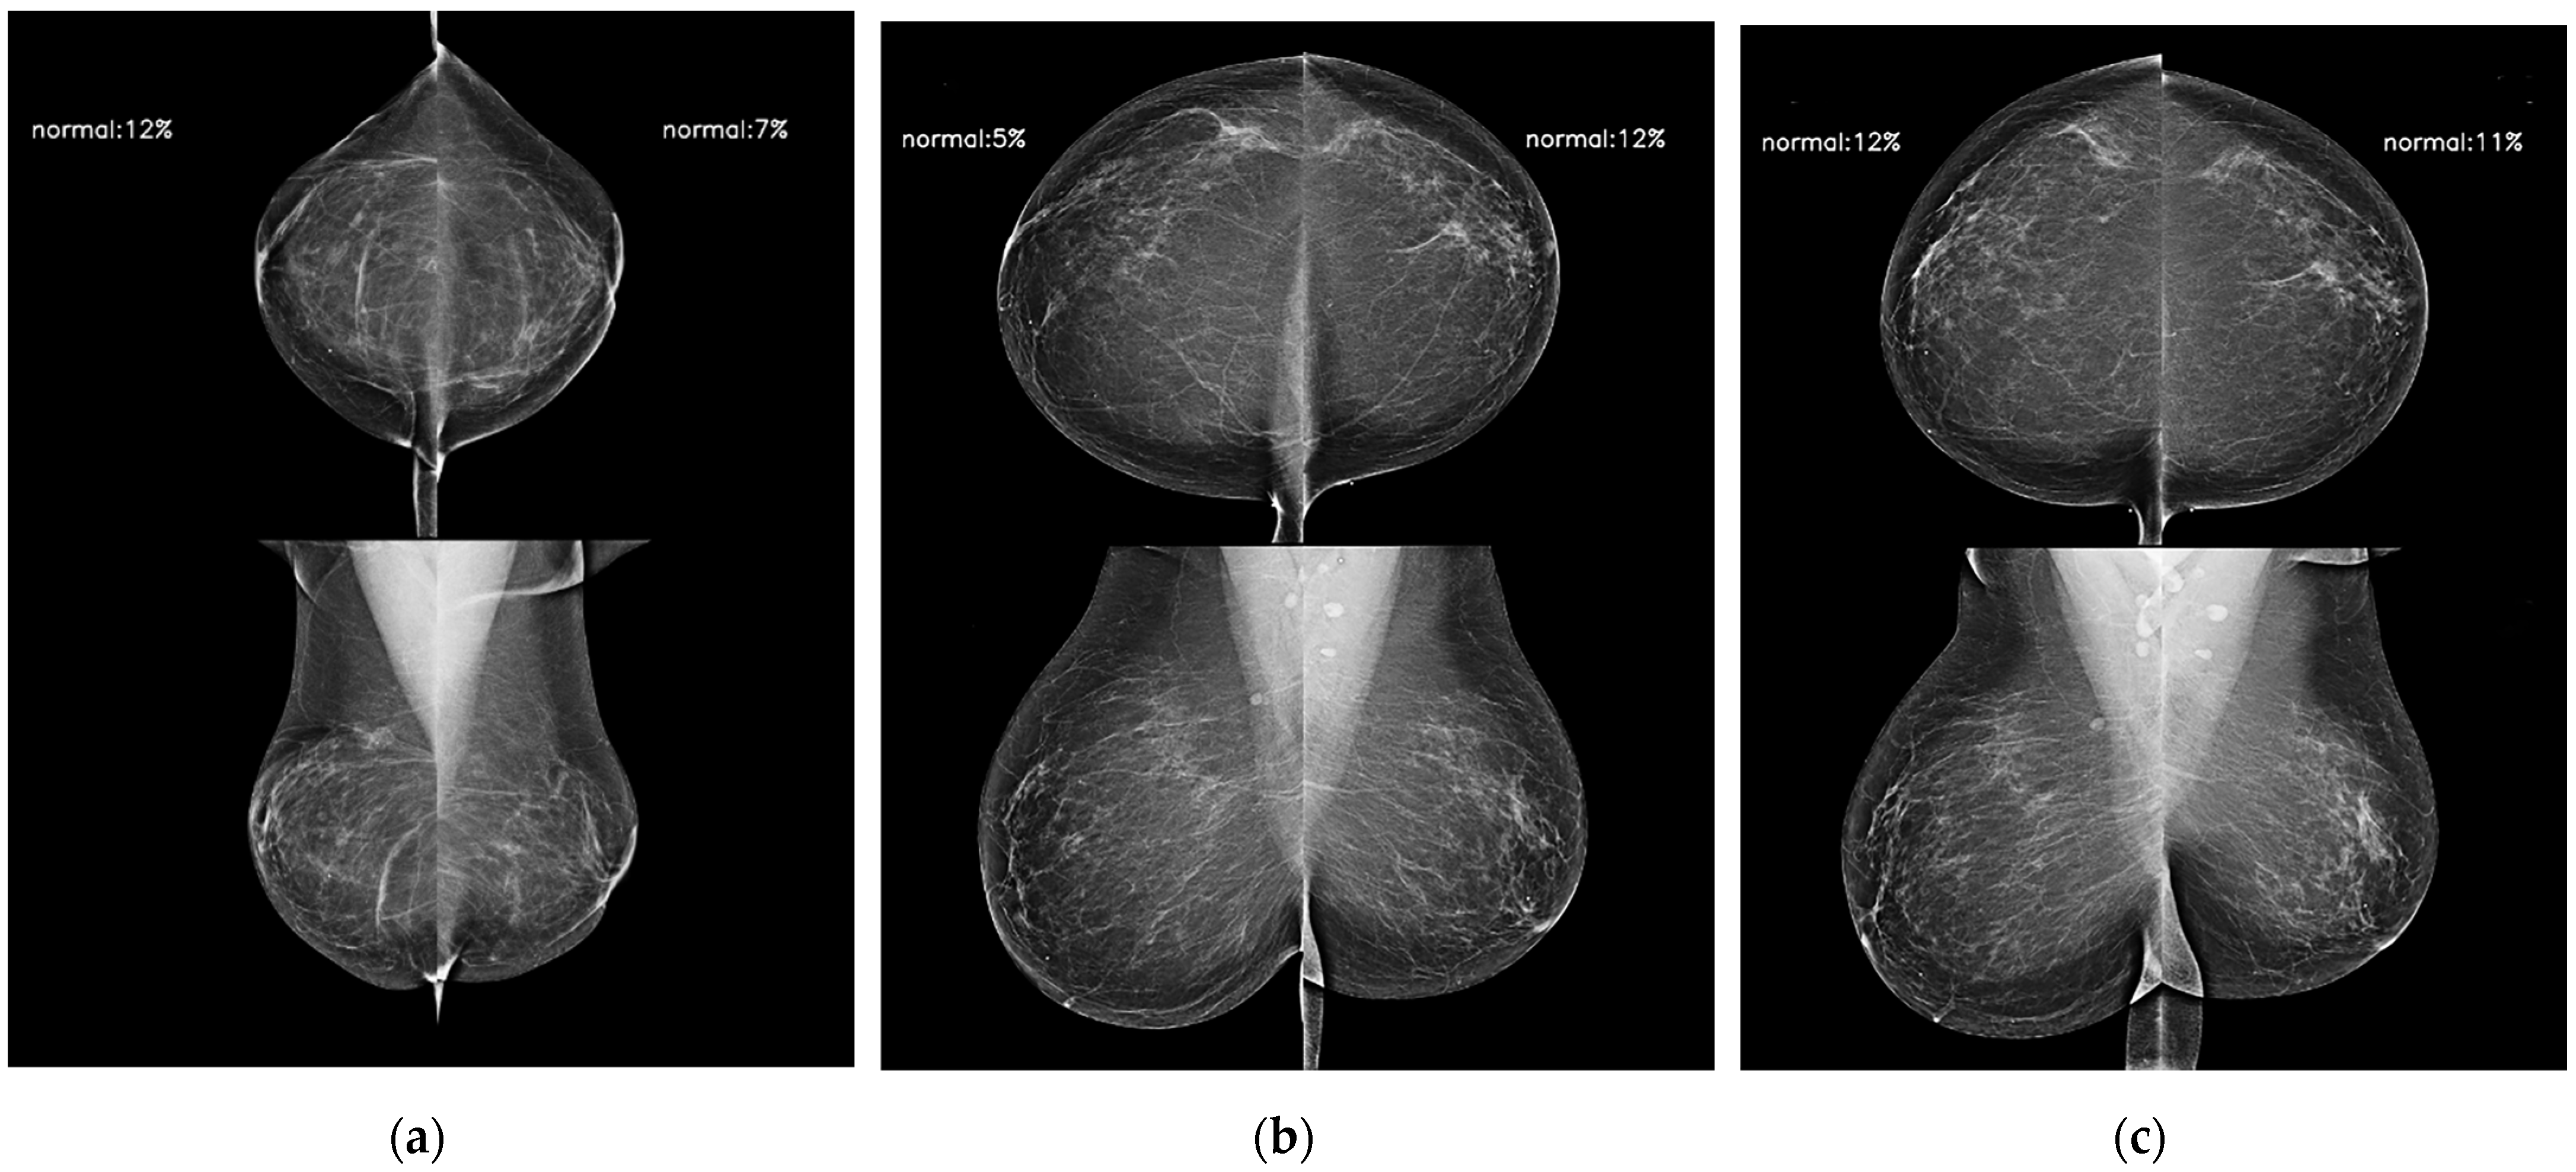

Figure 5.

AI model results for serial digital mammography images with AI scores used to predict future breast cancer in a 65-year-old woman with negative results during 5 years of follow-up. AI scores of bilateral breasts (a) 4 years ago, (b) 2 years ago, and (c) at the time of diagnosis were kept up to 0.12 all of the time.